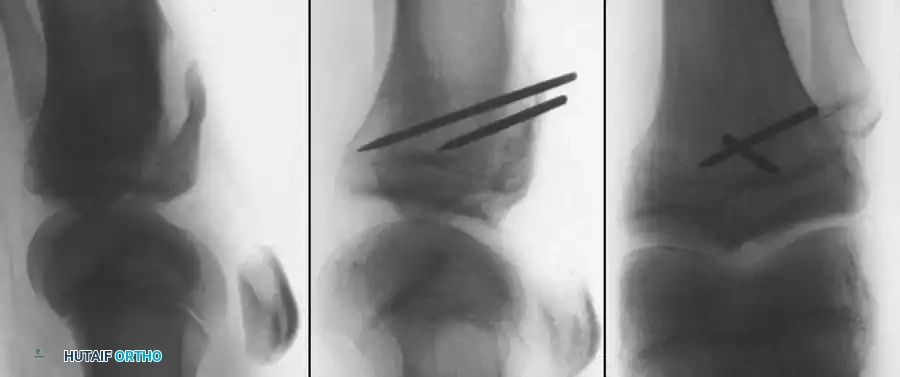

Classification (Meyers and McKeever)

The management of tibial eminence fractures is dictated by the Meyers and McKeever classification system, which assesses the degree of displacement and the presence of a cartilaginous hinge.

- Type I: Non-displaced or minimally displaced fracture. The bony fragment rests in its anatomical bed.

- Type II: The anterior portion of the eminence is elevated and displaced proximally, but an intact cartilaginous hinge remains posteriorly. The fragment resembles a bird's beak.

- Type III: Complete displacement of the fragment with no cortical or cartilaginous continuity. The fragment may be rotated.

- Type IV (Zaricznyj modification): Comminuted fracture of the eminence.

- Fixation: To avoid crossing the proximal tibial physis with rigid hardware (which could cause growth arrest or angular deformity), suture fixation is preferred.

- Pass a heavy, nonabsorbable suture (e.g., #2 FiberWire or Ethibond) through the most distal, robust portion of the ACL substance, just proximal to the bony fragment.

- Using an ACL drill guide, drill two parallel 2.0 mm tunnels from the anteromedial tibial metaphysis, aiming directly into the fracture crater. Crucial: Ensure the drill path remains entirely within the epiphysis if possible, or crosses the physis centrally and vertically to minimize the risk of growth arrest.

* Retrieve the suture limbs through the drill holes.

* Tie the sutures securely over a bony bridge on the anteromedial tibia while holding the knee in 20 degrees of flexion and applying posterior translation to the tibia to tension the ACL.

Arthroscopic techniques offer the advantage of minimal morbidity and excellent visualization of the joint space. Fixation can be achieved via:

* Fracture-based methods: Antegrade cannulated screws (only if the fragment is large enough and the patient is nearing skeletal maturity, avoiding the physis).

* Ligament-based methods: Retrograde suture passage using suture passers (e.g., Lasso) through the base of the ACL, shuttled through trans-epiphyseal drill holes, and tied over the anterior tibia.